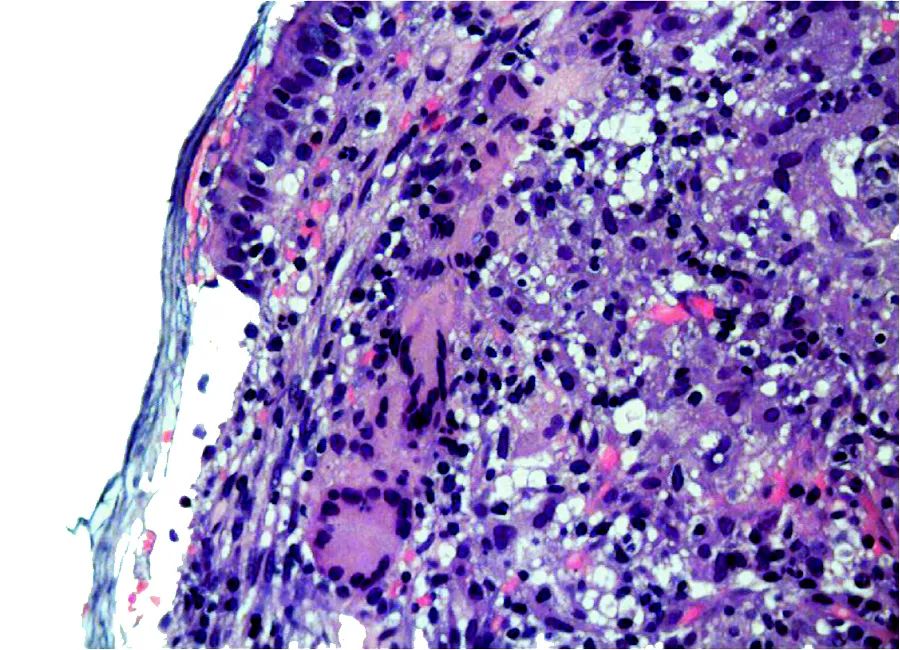

病理活检:肉芽肿形成